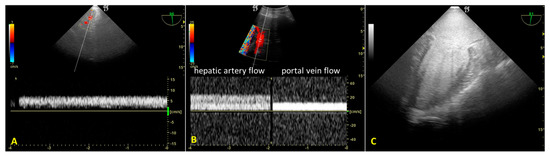

During A-NRP, we monitored hepatic re-perfusion with color Doppler US and laboratory tests. TEE revealed initial reduced hepatic artery blood flow (transgastric view) due to incomplete aortic occlusion and decreased hepatic perfusion pressure (Figure 3A). After complete aortic occlusion, hepatic artery blood velocity increased, and portal vein blood flow was sampleable. (Figure 3B) At the same time, blood lactates decreased from 9.4 mEq/L to 5.2 mEq/L. TEE also allowed us to observe the absence of blood flow in the left ventricle and atrium after complete aortic occlusion, as well as the lack of cardiac contractility, despite PM activity displayed on the electrocardiogram (Figure 3C).

Figure 3. (A). Transesophageal color Doppler echocardiography with transgastric approach during the initial phase of regional extracorporeal support. Slow hepatic artery flow is sampled due to incomplete aortic occlusion (continuous right hepatic artery flow velocity = 7 cm/s). Portal vein flow was absent. (B). Color Doppler ultrasound with convex probe after complete aortic occlusion. Right hepatic artery flow was increased (velocity 25 cm/s) and the portal flow was sampled (velocity 12 cm/s). (C). Absence of flow in the left ventricle and atrium after complete aortic occlusion (mid-esophageal two-chamber view).